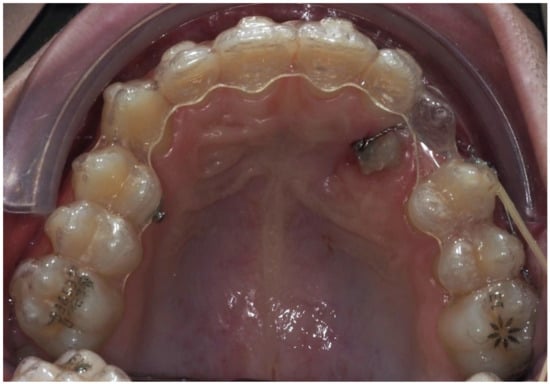

3.2. Representative Clinical Case

A 13-year-old male patient presented with Class II Division 2 malocclusion, a bilateral Class II sagittal relationship, and retroclined incisors. Cone-beam computed tomography revealed a palatally impacted maxillary left canine (tooth 23), with its cusp located palatally to the apical half of the left lateral incisor. The root exhibited significant apical curvature, extending toward the floor of the maxillary sinus (Figure 12 and Figure 13), making spontaneous eruption unlikely.

Figure 12.

Initial intraoral lateral photo.

Figure 13.

Impacted canine 23 with its cusp palatally positioned to the apical half of the left lateral incisor, with the root significantly curved and inserted into the maxillary sinus.